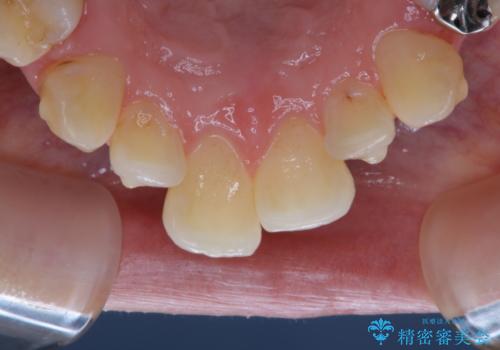

磨けているようでも、染出しをして目に見えるプラーク(歯垢)を確認することで、より正しいブラッシング方法を身につけることができます。インビザライン中は、歯にアタッチメントをつけるため、歯の表面がデコボコしてプラークが付きやすい状態になります。毎日のケアでしっかりと汚れを落として虫歯や歯周病・口臭のリスクを減らしていくことが大切です。定期的にメンテナンスを行い、ケアがどれくらい出来ているか確認したり歯科医院で専門的な機械や器具によるPMTCを行うことをおススメします。